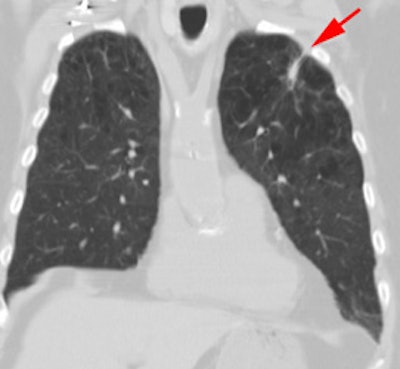

Vascular graft activity: The patient below had a prior graft repair of an ascending aortic aneurysm. Tracer uptake can be seen in the ascending aortic graft (black arrows). The patient also has a left upper lobe lung cancer (red arrows). |

|